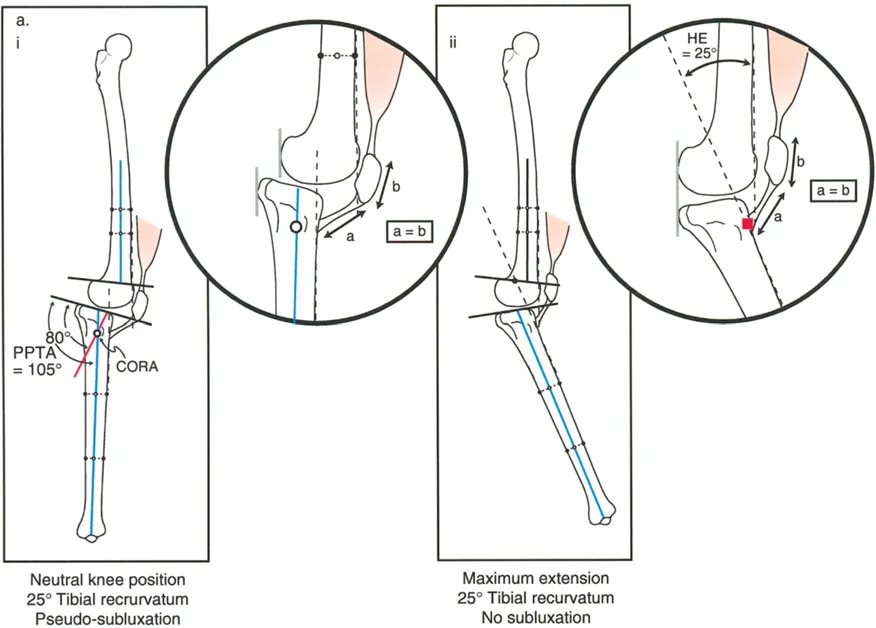

- في بعض الحالات، قد يحدث خلع جزئي للركبة (subluxation)، خاصة في حالات الارتداد الظنبوبي الشديد.

- تقييم مدى الحركة: يتم قياس مدى حركة الركبة، بما في ذلك أقصى تمدد وأقصى انثناء. يتم تحديد درجة فرط التمدد (HE - Hyperextension) أو درجة تقلص الانثناء الثابت (FFD - Fixed Flexion Deformity).

- زاوية الانحناء القريبة للظنبوب (PPTA - Proximal Posterior Tibial Angle): تقيس زاوية الجزء العلوي من عظم الساق. القيمة الطبيعية حوالي 80 درجة. الزيادة في هذه الزاوية (أكثر من 80 درجة) تشير إلى ارتداد ظنبوبي.

- مركز دوران الزاوية (CORA - Center of Rotation of Angulation): يتم تحديد هذا النقطة على الأشعة السينية لتحديد مكان التشوه العظمي بدقة، وهو أمر بالغ الأهمية لتخطيط عملية قطع العظم.

- الركبة الارتدادية بسبب الارتداد الظنبوبي:

- إذا كانت درجة فرط التمدد (HE) تساوي درجة الارتداد الظنبوبي (PPTA > 80°)، فهذا يعني أن التشوه كله ناتج عن عظم الساق.

- في هذه الحالة، يكون مركز CORA في الجزء القريب من عظم الساق.

- الركبة الارتدادية بسبب الارتداد الظنبوبي مع تقلص انثناء:

- إذا كان هناك ارتداد ظنبوبي (PPTA > 80°) ولكن لا يوجد فرط تمدد سريري (HE = 0°)، فهذا يشير إلى وجود تقلص انثناء مصاحب.

- إذا كان فرط التمدد (HE) أقل من درجة الارتداد الظنبوبي، فهذا يعني وجود تقلص انثناء جزئي.